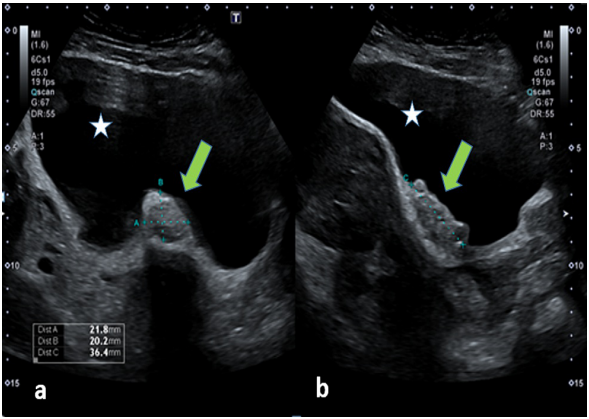

根据患者目前的症状,在间隔五年后患者再次接受了骨盆超声检查,结果显示子宫严重前倾并增大,伴有多个大小不等的壁内和浆膜下肌瘤。膀胱底部显示一个分叶状、边界清晰的低回声固定肿块,大小为22 x 20 x 36 mm,无明显的血管分布(图1)。双侧卵巢均正常,盆腔未见游离液体。根据超声检查结果,建议患者行膀胱镜检查;然而,患者接受了骨盆 MRI 以更好地表征病变。

图1. 超声图像。(a) 横向和 (b) 纵向图像:沿着膀胱底部的清晰分叶状低回声病变(绿色箭头)(星号)